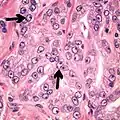

Intraductal carcinoma of the prostate with an infiltrative growth pattern may be morphologically difficult to distinguish from invasive cancer. One focus shows comedonecrosis (arrow), morphologically suggesting Gleason pattern 5 invasive carcinoma (a haematoxylin and eosin, b CK5/6)[19]

Intraductal carcinoma of the prostate with very patchy basal cells identified by immunohistochemistry. At least some of the glands lacking basal cell immunoreactivity represent intraductal rather than invasive carcinoma (a haematoxylin and eosin, b CK 5/6)[19]